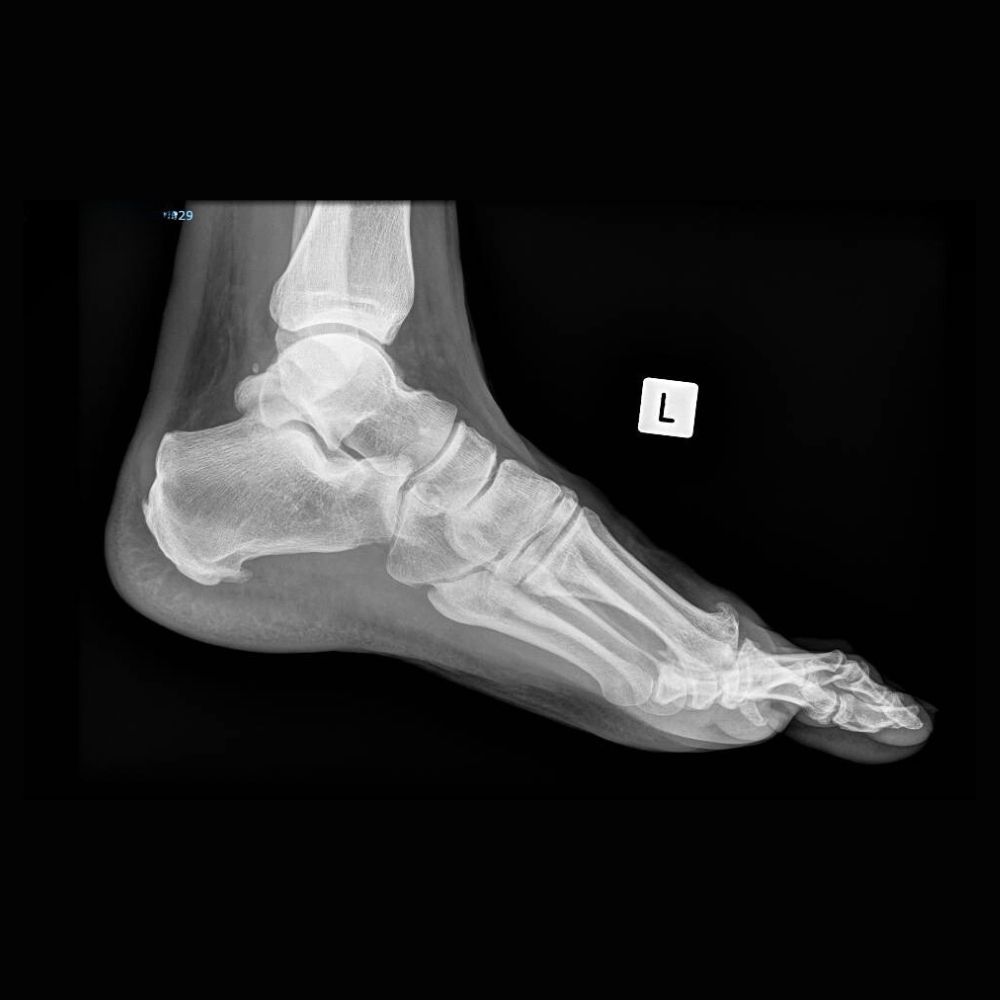

Adult with Fusion (Arthrodesis) of the Left Hallux Rigidus (Osteoarthritis of the Big Toe)